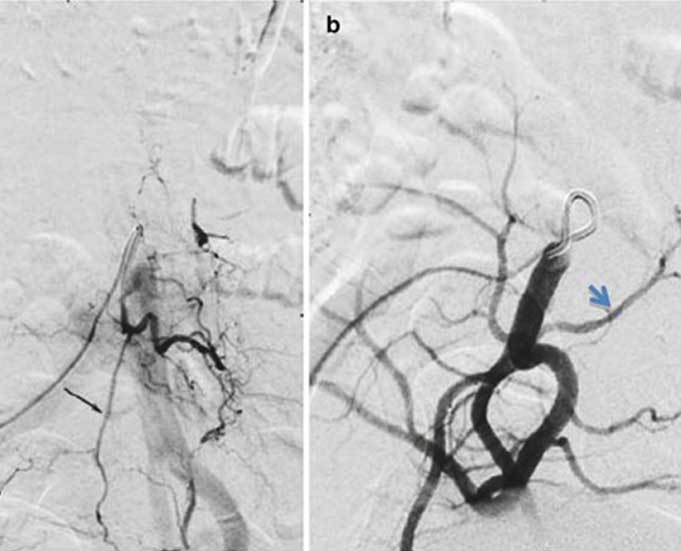

Spinal vascular malformations encompass a range of disorders that often result in an intermittent or progressive myelopathy. Standard magnetic resonance imaging (MRI) may not identify the vascular abnormality and can be normal in the early stages of the disorder. The myelopathy can be exercise dependent initially and can spontaneously remit.

However, if not identified, it can lead to a progressive disabling myelopathy, which is difficult to reverse even after correction of the spinal vascular abnormality. A negative formal spinal angiogram does not completely exclude a spinal vascular malformation, as there is a large range of abnormalities that extend throughout the length of the spine and beyond into the cerebral vasculature and pelvic vasculature.